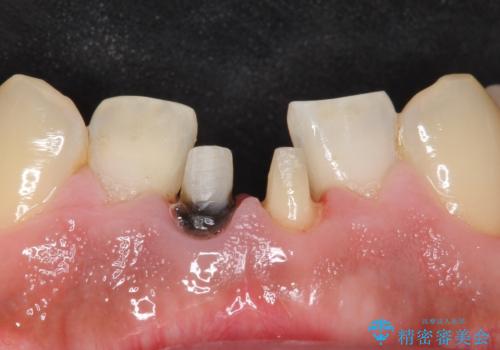

- 下の前歯の色が気になることを主訴に来院された患者様です。

下の前歯は金属の土台により黒くなり、隣の歯も神経が死んで暗く変色していました。

神経が死んでいる歯の根管治療を行った後、セラミッククラウンによる補綴治療を行いました。